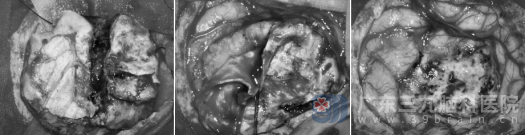

面对这个紧邻重要脑功能区(接近中央前回)、体积不小的肿瘤,神经外十科团队迅速组织病例讨论,制定了周密的手术方案。在向患者家属详细解释病情并取得同意后,一场历时4个多小时的精细手术紧张有序地展开。手术室内,专家团队凭借精湛的显微神经外科技术,在保护正常脑组织、血管和神经功能的前提下,成功将肿瘤完整切除。